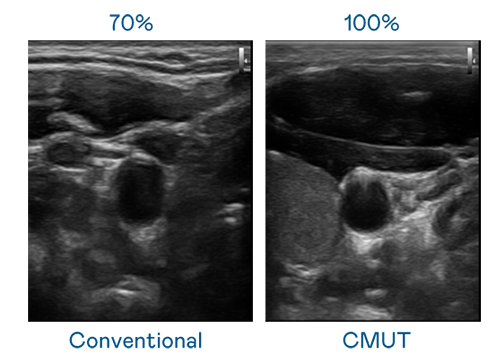

CMUT 技術是一種用電容式微機電元件來產生超音波訊號的技術。與傳統 PZT 壓電式技術相比,CMUT 頻寬增加 30%,更寬頻的超音波訊號讓影像解析度大幅提升,是實現高影像品質醫療超音波掃描、促進精準醫療發展的關鍵技術。

超音波影像的解析度高低,首先取決於探頭能發出的訊號頻寬。BBIN视讯 CMUT 可提供高清晰的超音波訊號,提供高頻寬、高靈敏度、影像紋理細節更高的超音波影像,協助醫護人員縮短影像判讀時間及利用精準的醫療影像進行診斷。